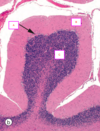

Label A&B of the hippocampus [2]

A: CA2 B: CA3 Both undergo atrophy in epilepsy

The CA areas of the hippocampus are all filled with densely packed [] cells that make up the stratum pyramidale

The CA areas are all filled with densely packed **pyramidal** cells that make up the stratum pyramidale